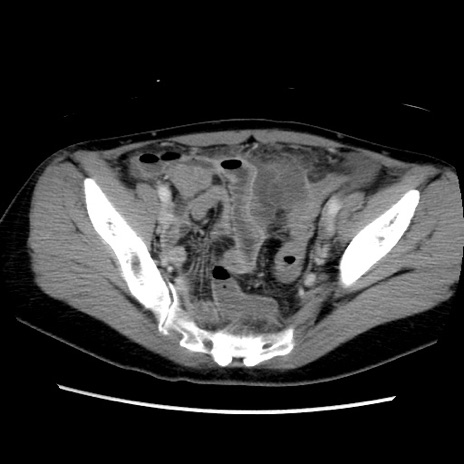

症例39(横断像)

【症例】40歳代女性

【主訴】上下腹部痛

【現病歴】2日目から下腹部痛あり。夜間は痛みで眠れなかった。昨日より上腹部痛と下痢が出現。臥位で痛みは軽快したため、休んでいた。本日になって臥位でも立位でも痛みが強くなってきたため救急要請。

【既往歴】子宮内膜症

【身体所見】部:平坦・軟、左上下腹部に圧痛あり、反跳痛あり。

【データ】WBC 21800、CRP 26.78